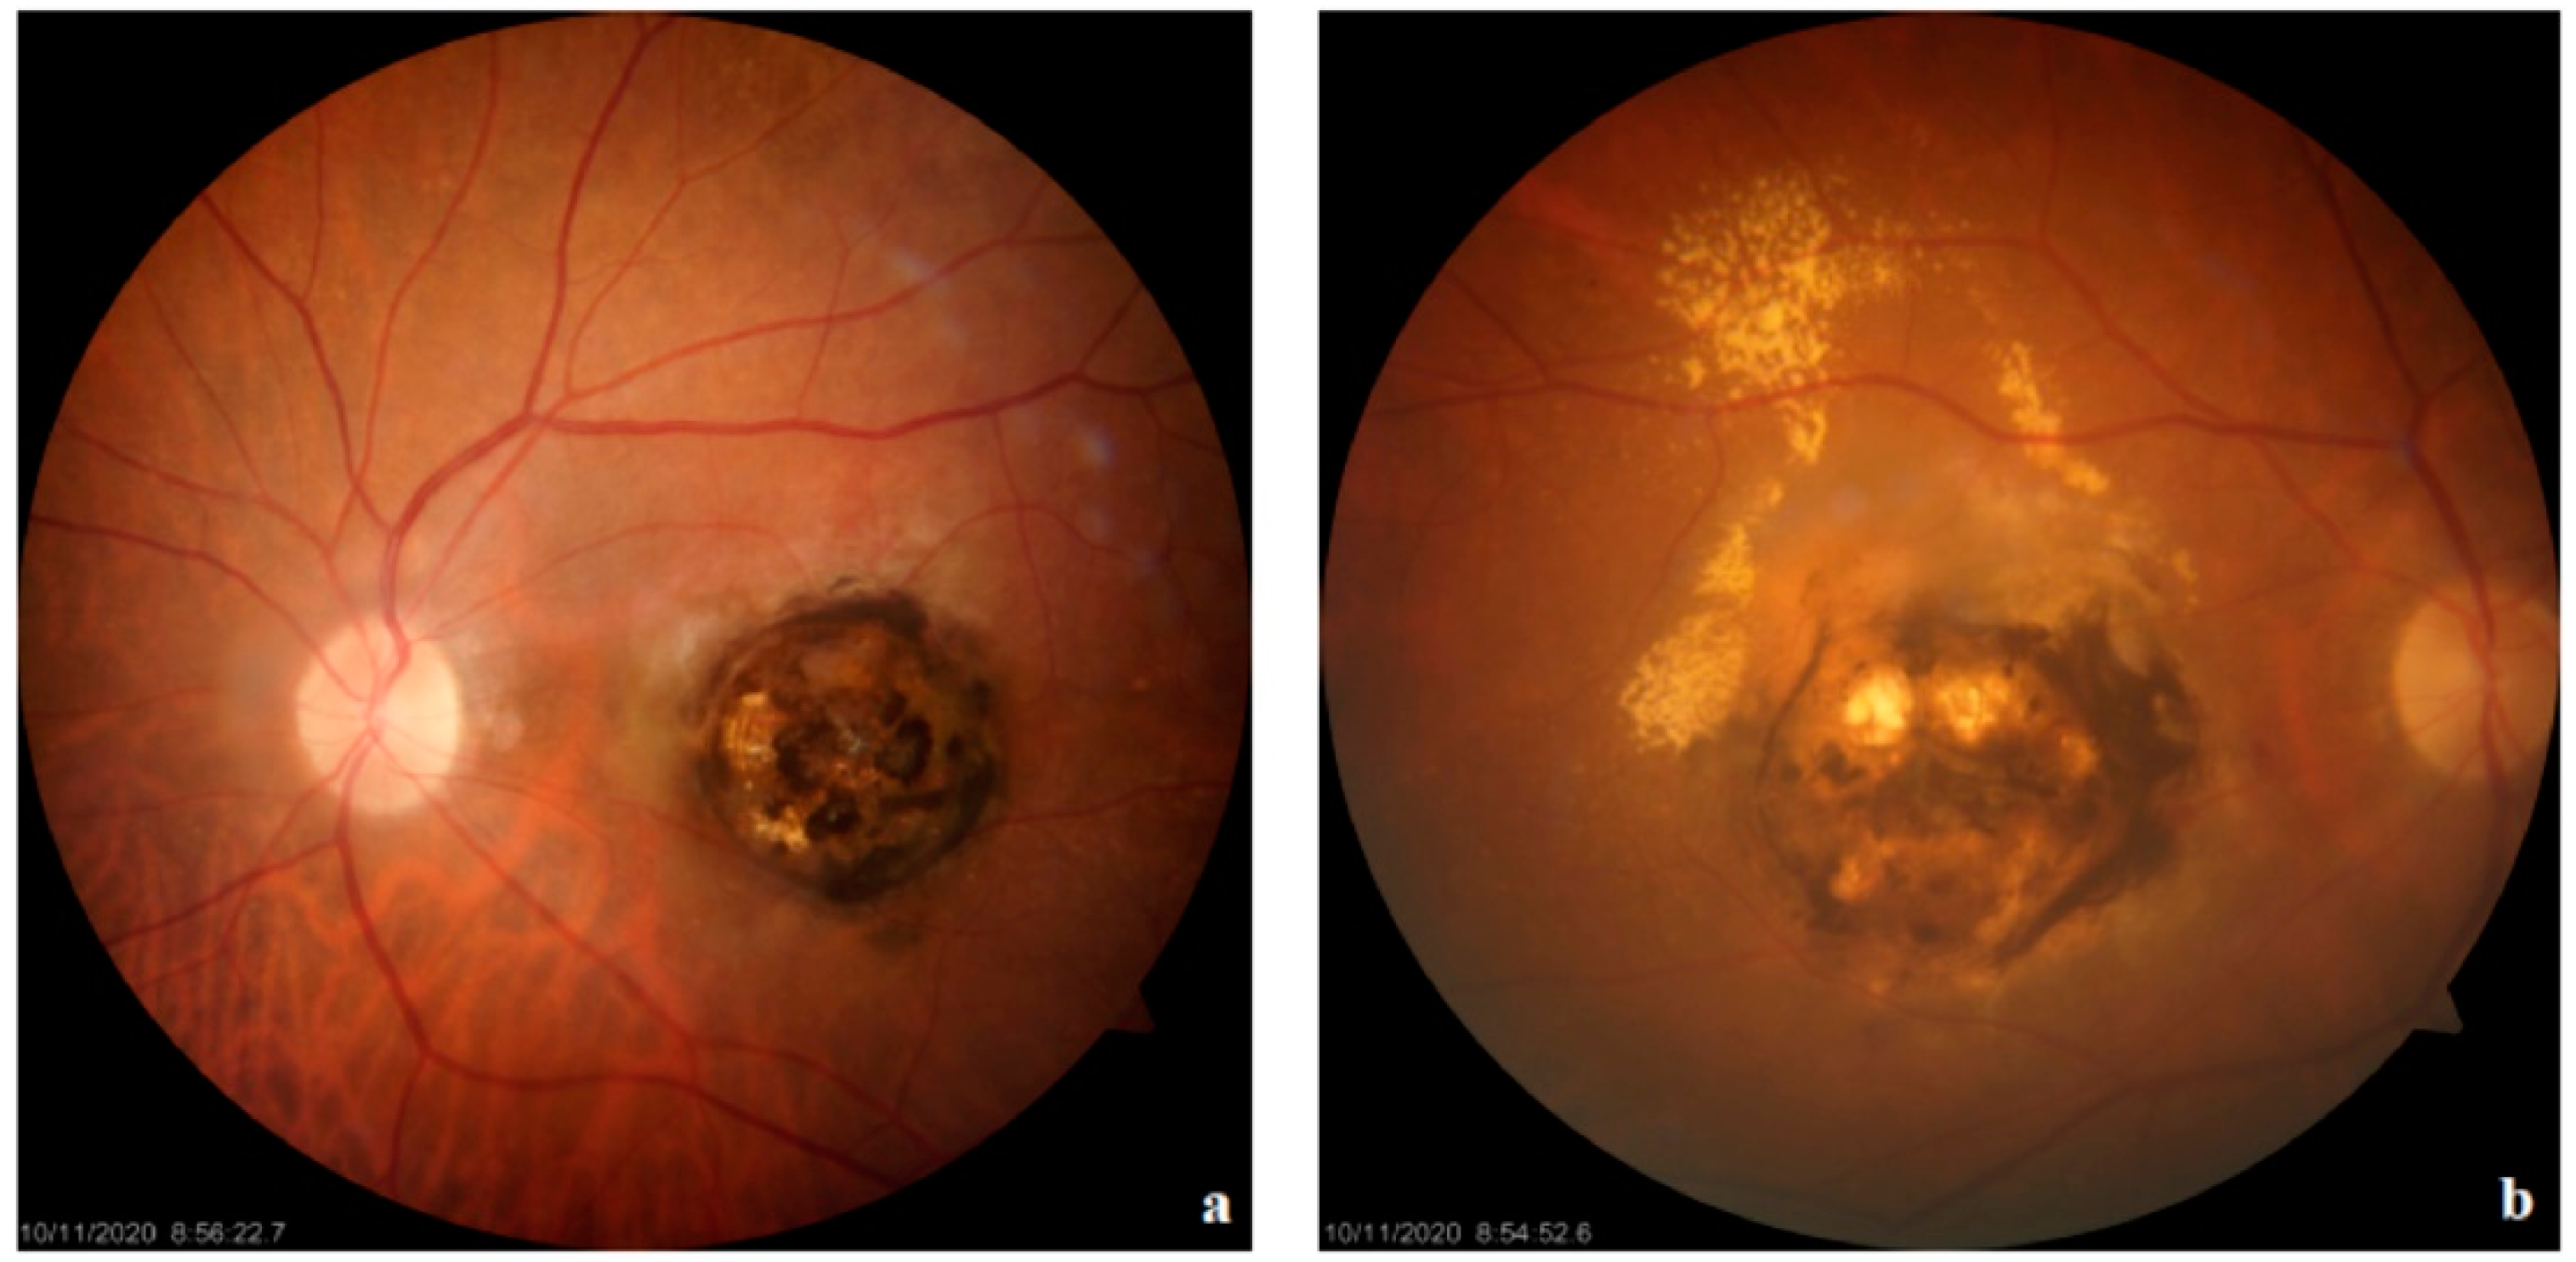

3.2. Clinical Manifestation of Ocular Toxoplasmosis

| Active Lesion | Gray-white necrotic foci in posterior pole with fuzzy borders; surrounding inflammation and hemorrhage | Subtle hyper/isoautofluorescence; thickening and detachment of posterior hyaloid over the lesion with irregular hyperreflective deposits | Early hypofluorescence, late progressive leakage at lesion margins; possible optic nerve head hyperfluorescence, vessel leakage, and vascular sheathing | Hypofluorescence; multiple satellite dark dots extending beyond the active retinal lesion; localized choroidal hypoperfusion | Increased intraretinal reflectivity with disorganization of neuroretinal layer boundaries corresponding to the area of retinitis; thickened and hyporeflective choroid beneath the active lesion; posterior hyaloid thickening with irregular hyperreflective deposits over the lesion | Hyporeflectivity of the lesion with diffuse choroidal dilation and many collateral vascular branches surrounding; decreased flow in outer retina and choriocapillaris | Fuzzy lesion margins, surrounding retinal edema; “headlight in the fog” appearance due to vitritis; ICGA shows multiple satellite dark dots |

| Inactive/Scar Lesion | Well-defined pigmented scar with sharp margins, often with central atrophy | Hypoautofluorescent | Early hypofluorescence due to pigment blockage or window defect, late staining at margins | Hypofluorescence; disappearance of satellite dark dots | Disorganized retinal layer reflectivity beneath a thin, hyperreflective choroid; RPE-choroid complex atrophy; persistent “hourglass configuration” with RPE changes and retina-RPE approximation | Marked reduction or absence of flow signal in all layers within the affected area | Clear boundaries, no signs of active inflammation; OCT shows tissue atrophy and “hourglass configuration” |

| Recurrent Lesion | New active lesion typically adjacent to old inactive pigmented scar (satellite lesion) | Mixture of hyper/isoautofluorescence (new lesion) and hypoautofluorescence (old scar) | Early hypofluorescence in new lesion area, late hyperfluorescence with leakage | Hypofluorescence; reappearance of satellite dark dots around new lesion | New area of retinal thickening adjacent to old atrophic area; posterior hyaloid thickening and epiretinal membrane formation | Changes in flow signal in new lesion area: increased in inner retina, decreased in outer retina and choriocapillaris | Coexistence of new active lesion and old scar; OCT shows both acute and chronic changes |

| Congenital Lesion | “Horseshoe” or ring-shaped macular scar | Hypoautofluorescent scar | Hypofluorescence in scar area | Hypofluorescence in scar area; possible choroidal filling defects | Macular retinal atrophy, disorganized retinal structure, possible outer retinal tubulation | Reduced or absent flow in all retinal layers and choriocapillaris in the scar area | Typical macular scar morphology; severe visual impairment from birth |